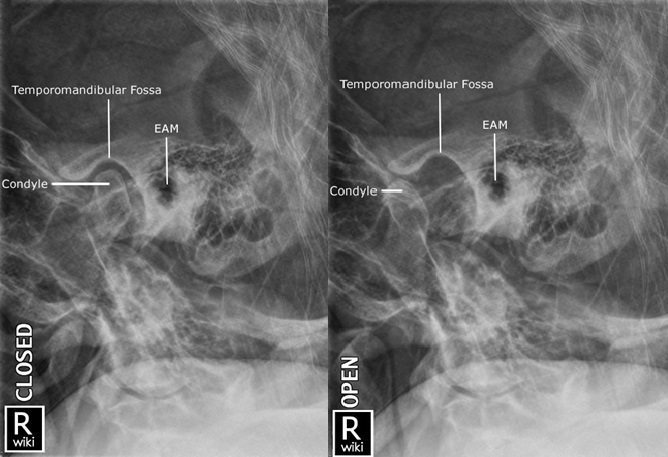

4. TMJ Radiography

1) Adult Lateral Oblique - Closed/Open Mouth

2) Gleb 4/7 position

![]() |

• 하악과두는 앞뒤로 볼 때 턱관절 주머니의 정가운데에서 앞쪽(관절융기 쪽)에 위치 • 위아래로 볼 때 턱관절 주머니의 전체 높이의 절반 정도에 위치 |